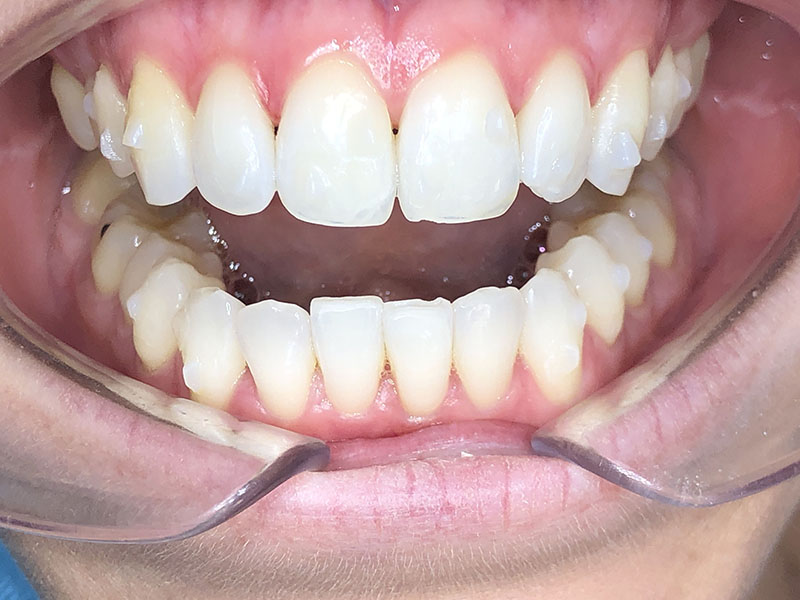

Patiente de 34 ans venue au cabinet pour une réhabilitation de son sourire suite à une récidive de son traitement d’orthodontie survenue pendant son adolescence, à cause du non-remplacement de sa contention perdue. Elle avait eu dans le passé une proposition de traitement par facettes pour réaliser l’alignement qu’elle avait refusé, ne voulant pas que l’on touche à ses dents.

À l’examen clinique, la patiente est en classe I d’Angle molaire bilatérale, indication idéale pour les traitements d’alignement simples que peuvent réaliser les omnipraticiens formés à cette thérapeutique.

Aucune autre pathologie ni problème dentaire ne furent relevés, en dehors d’un nettoyage préalable.

Au bout du port de celles-ci, nous avons constaté un défaut dans le positionnement des dents, probablement dû à la difficulté de certains mouvements de tipping et un manque d’alignement des milieux.

Il a été décidé de réaliser une série de finitions supplémentaires pour parfaire le résultat.